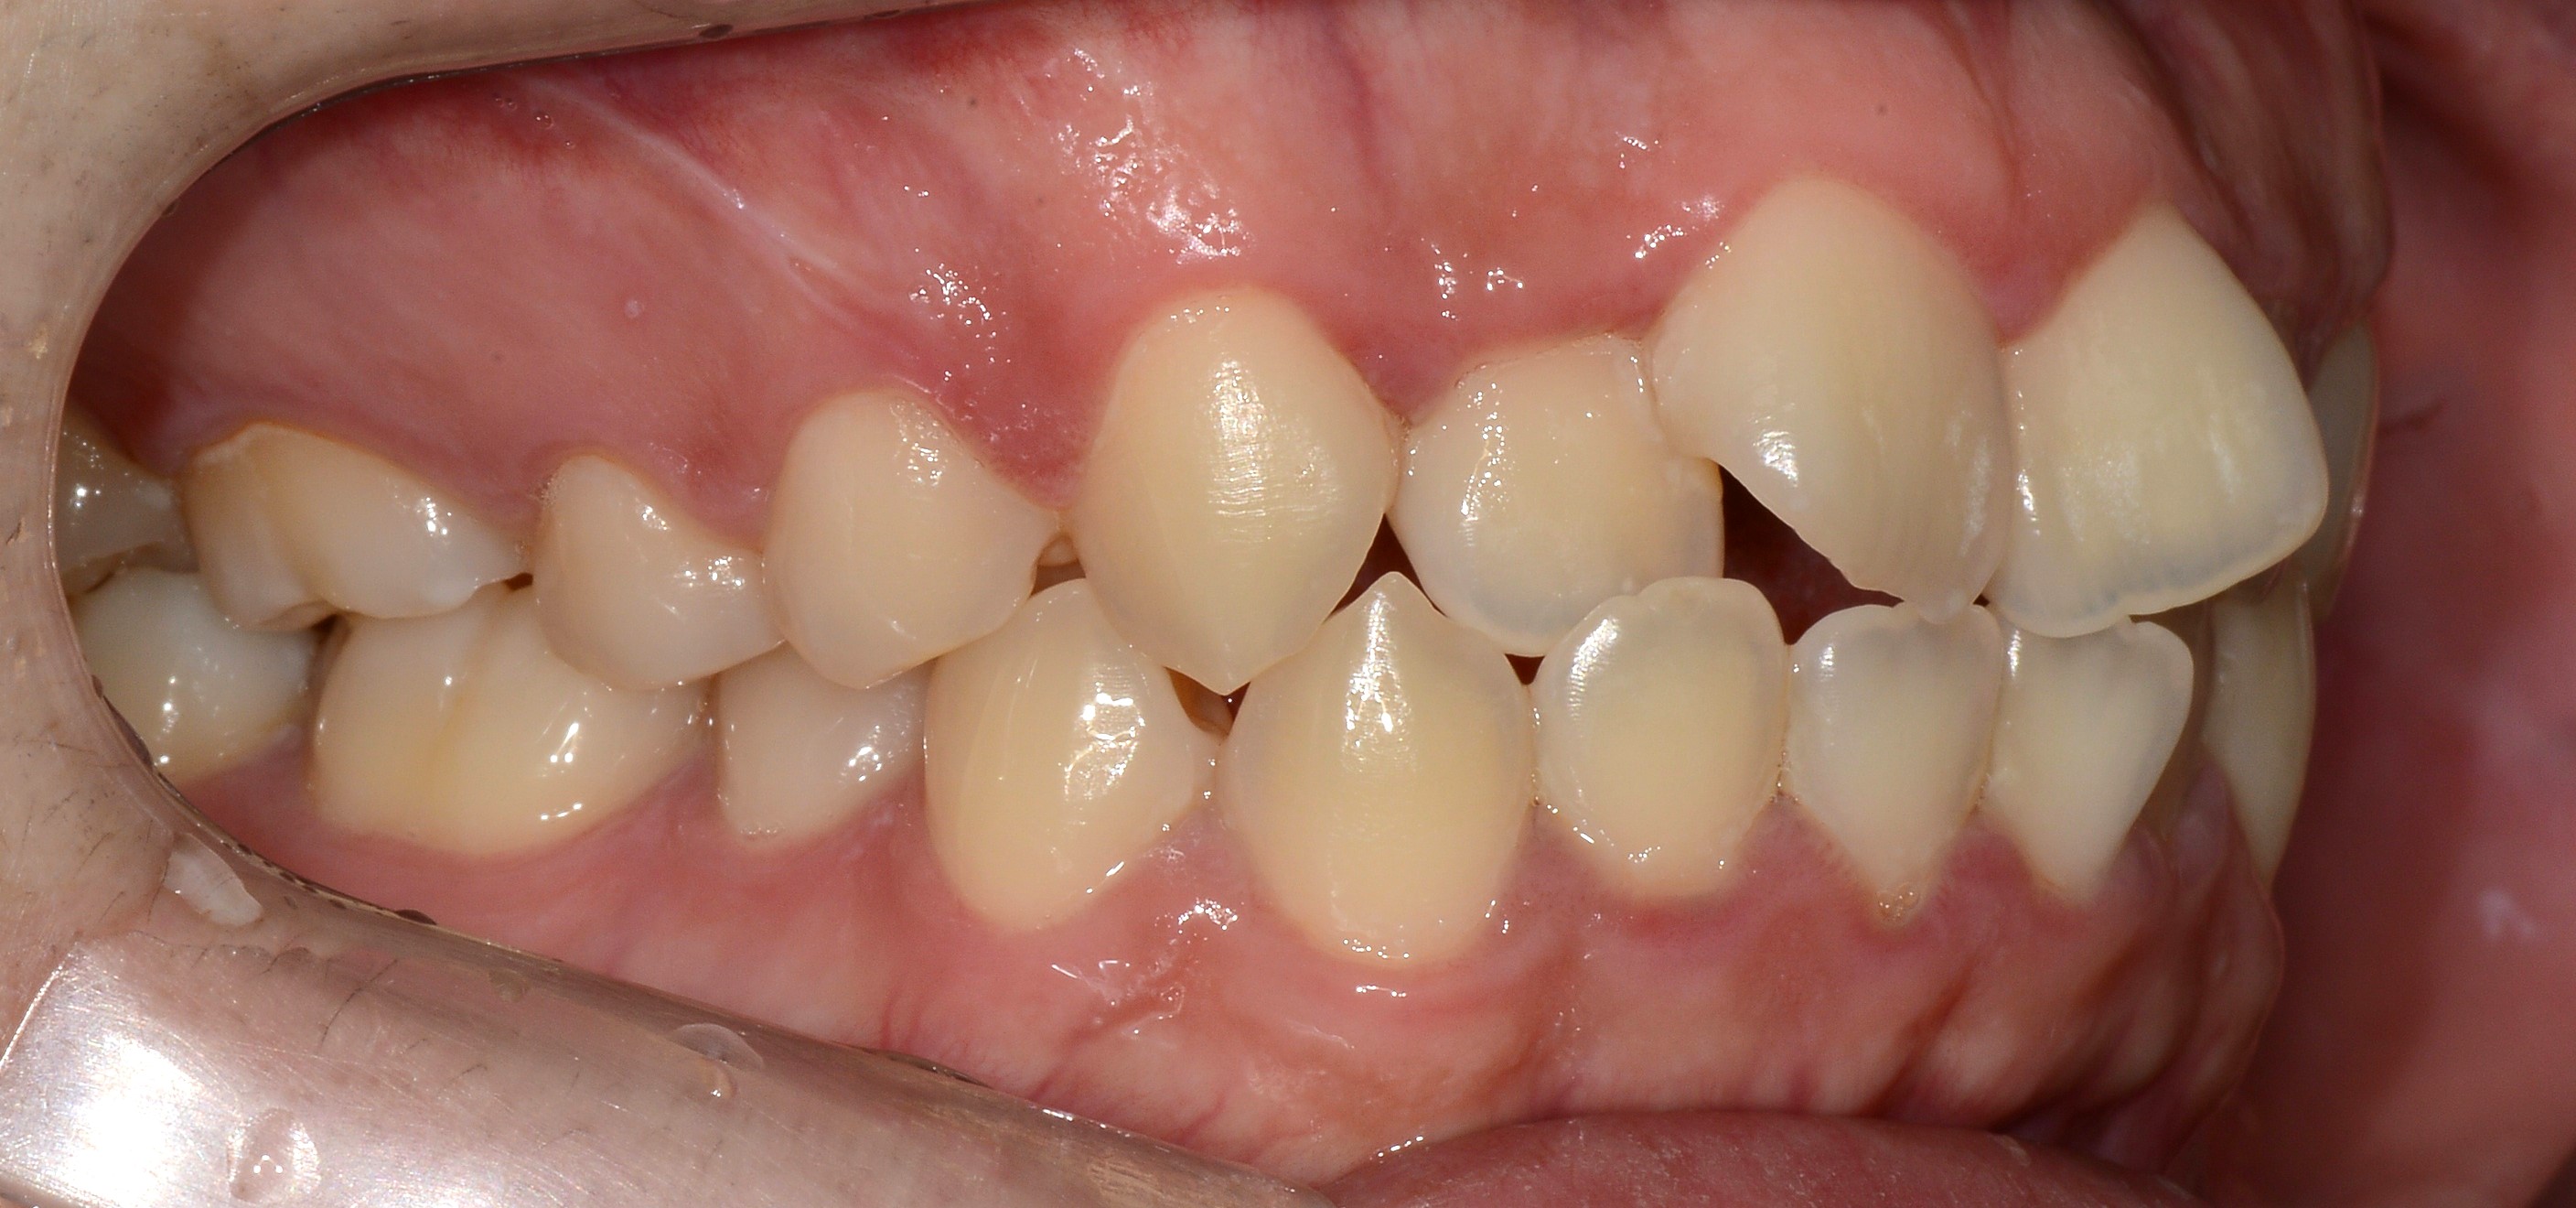

치료 후 사진입니다.